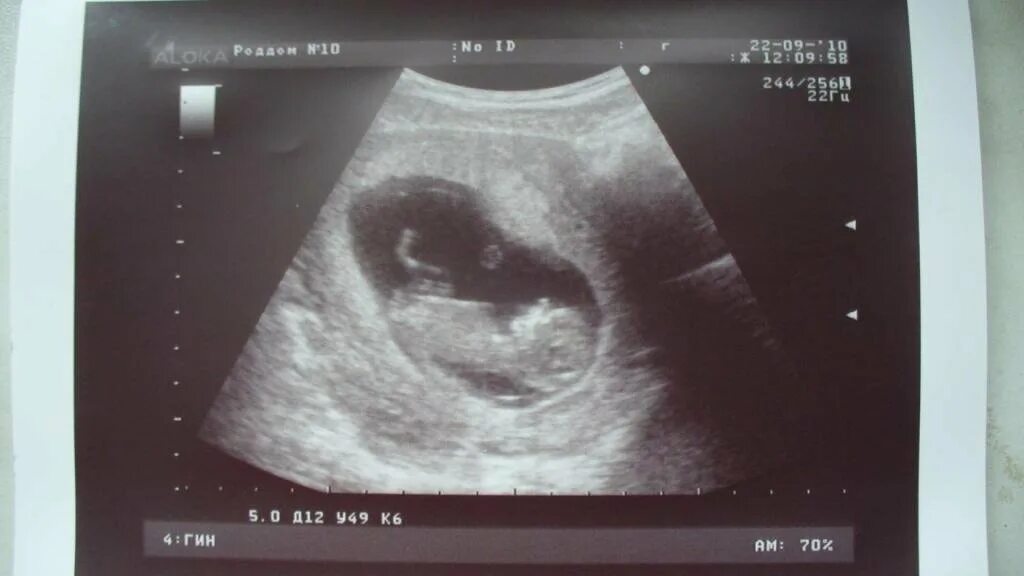

11 недель и 5 дней